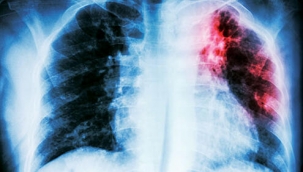

Covid-19 enfeksiyonu sonrası zatürre gelişme riski yüksek

Pandemi Döneminde Dünyada Zatürre Vakaları Artış Gösterdi